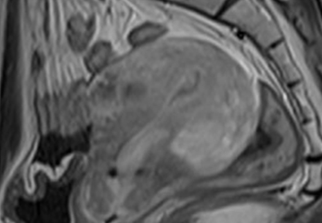

자궁근종 비수술 하이푸 치료 후 분만사례입니다. 자궁근종 하이푸 치료는 자궁근종 부위만 선택적으로 치료하는 시술로 자궁근종 전체적으로 시술하였습니다. 8cm 액화변성 자궁근종 하이푸 치료 시간은 57분이...